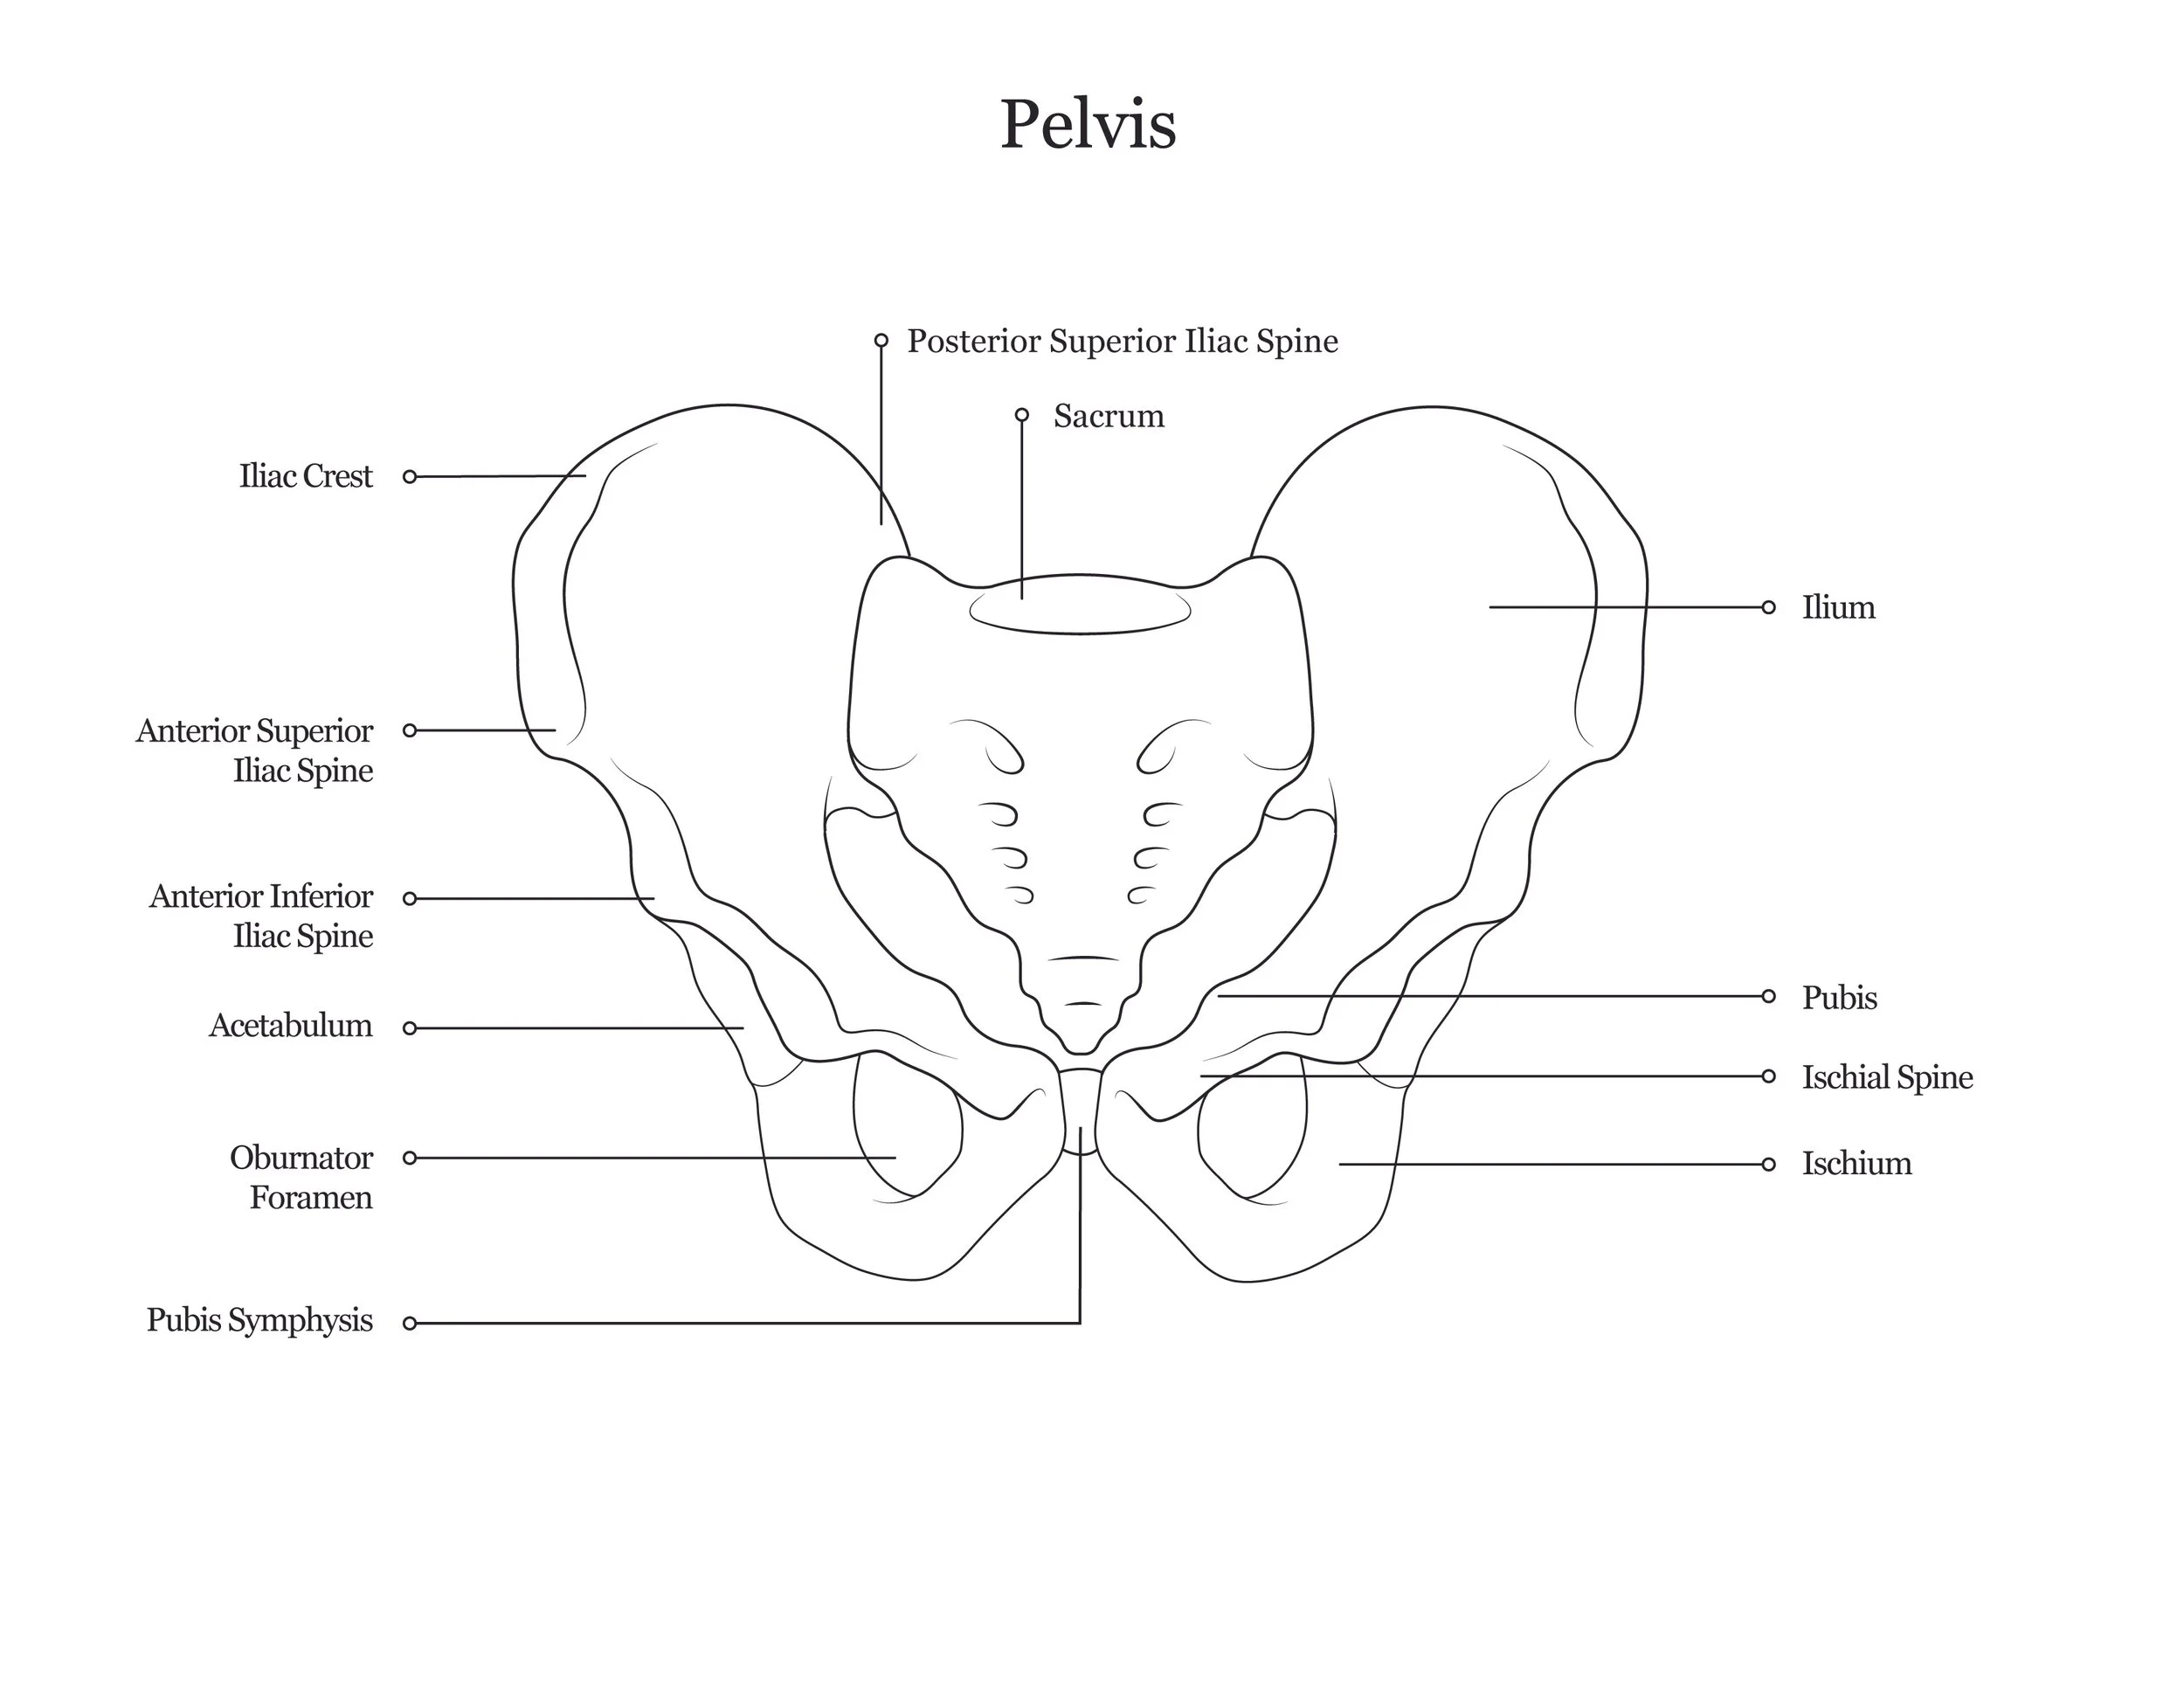

A series of anatomical illustrations created for Arcadia University’s Biology Department.

This project involved illustrating a series of diagrams for a cat dissection manual, focusing on skeletal and muscular anatomy. I consolidated multiple reference sources and firsthand specimen observation into a cohesive visual system for instructional use. Illustrations were refined iteratively to ensure anatomical accuracy, consistency, and clarity for students.